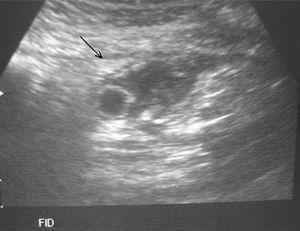

Se presenta el caso de un niño de 13 años que acude a urgencias con un cuadro de dolor en fosa ilíaca derecha y fiebre en las últimas 36 h. Como antecedente de interés destaca una intervención de apendicitis aguda mediante laparotomía hace un año. La ecografía abdominal muestra una estructura quística alargada en fosa ilíaca derecha, de aproximadamente 10 mm de diámetro, junto con una mínima cantidad de líquido libre (fig. 1). En la TC se apreciaban importantes cambios inflamatorios a nivel de fosa ilíaca derecha que se extendían hasta la pared abdominal anterior (fig. 2).

Figura 2.TC que muestra importantes cambios inflamatorios en fosa ilíaca derecha.